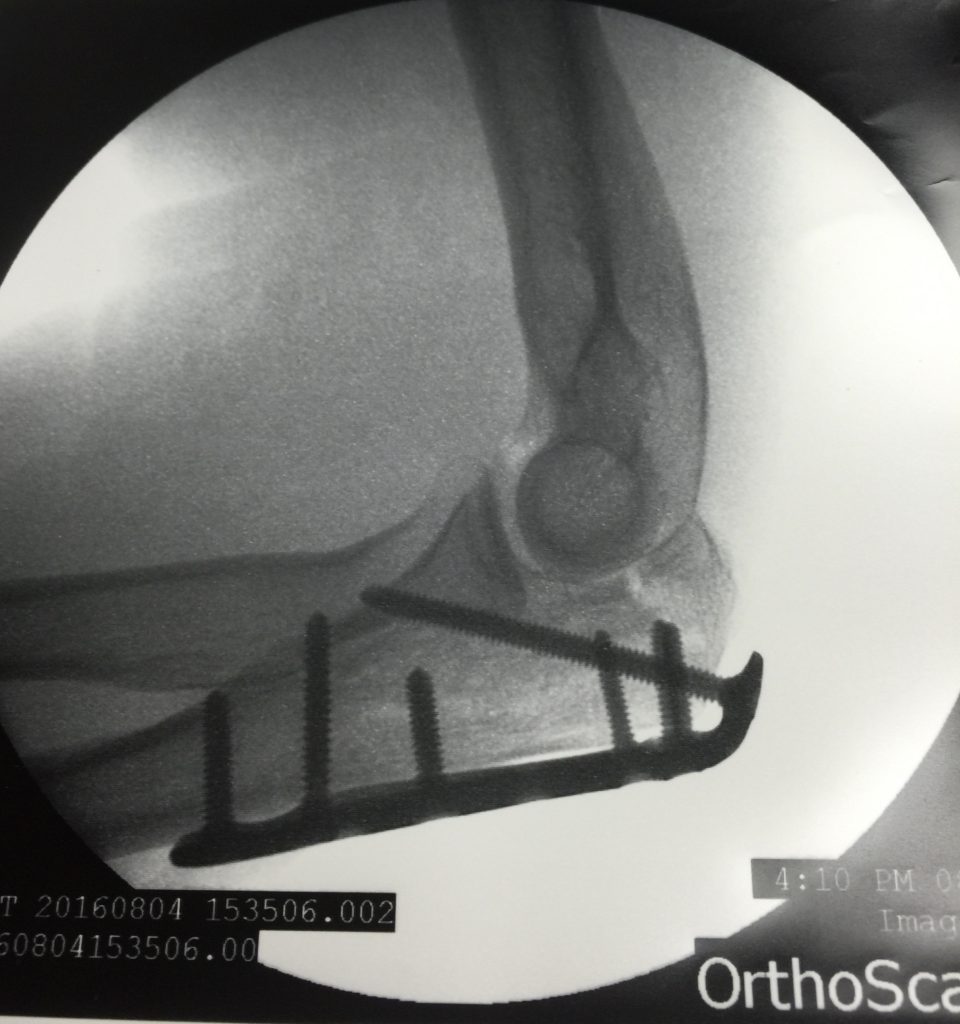

After surgery on my elbow – which included inserting a metal plate and eight screws into my arm – then physical therapy, the doctor said he was not happy with my progress, at all. If I would let him, he would operate on me again tomorrow.